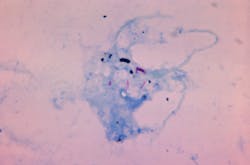

Bacterial culture is still commonly used to diagnose TB and to identify drug-resistant TB cases in much of the world. However, bacterial culture tests can take several weeks to provide a final result and are unable to detect a substantial fraction of individuals with active TB disease, delaying the decision to start and end anti-TB treatments.

More recently developed molecular tests can reduce the time required for TB diagnosis, but also exhibit poor ability to detect certain manifestations of TB disease and are not useful in monitoring patient responses to anti-TB therapy.

“Our test has several advantages over currently existing TB tests, including the gold-standard of bacterial culture,” says Tony Hu, the Weatherhead Presidential Chair in Biotechnology Innovation at Tulane University School of Medicine. “It requires only a small blood sample and directly measures TB-derived proteins to detect all forms of TB disease, including those missed by most other available TB tests. Notably, this approach can discriminate TB cases from those caused by related pathogens that produce similar symptoms but require different treatments.”